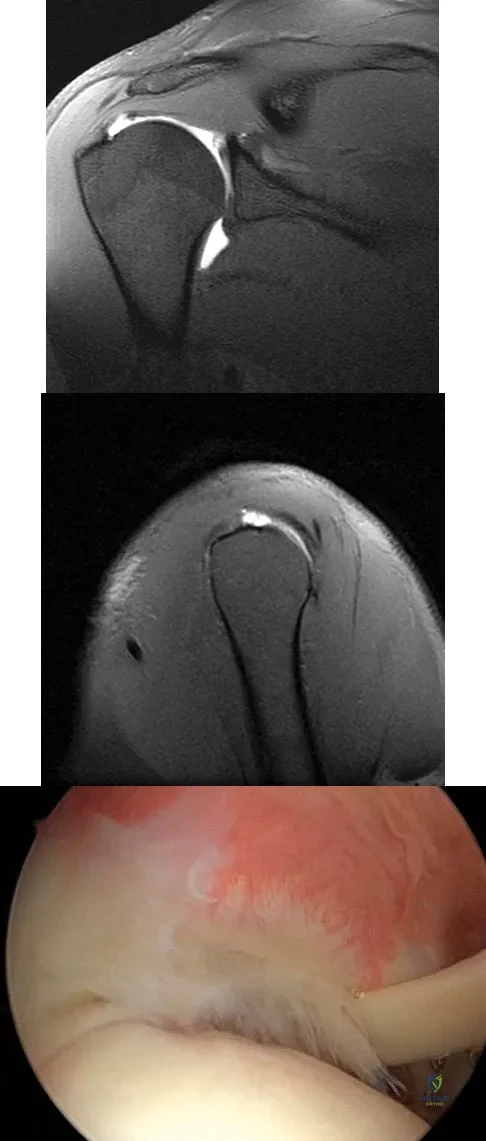

A 21-year-old collegiate pitcher has had pain in his dominant shoulder for the past 3 months despite management consisting of rest, rehabilitation, and an analysis of throwing mechanics. An arthroscopic photograph from the posterior portal is shown in Figure 10. The biceps anchor to the bone was not detached to probing. Treatment of the lesion to the left of the cannula should consist of arthroscopic

The lesion is a variation of a type I superior labrum anterior and posterior lesion; therefore, appropriate treatment is simple debridement. Biceps tenodesis or release is not indicated because the biceps tendon and anchor are intact. There is no indication for labral repair or capsulorraphy. Beaty JH (ed): Orthopaedic Knowledge Update 6. Rosemont, IL, American Academy of Orthopaedic Surgeons, 1999, pp 261-270.

A 23-year-old man who is a competitive overhead athlete has shoulder pain. Based on the pathology shown in Figure 47, what treatment option would yield the highest satisfaction and return to overhead sports?

The patient has a classic type II SLAP tear that will respond best to arthroscopic repair. Labral debridement has been shown to lead to predictably poor results, and biceps tenodesis and tenotomy may be appropriate for an older patient who is not a competitive overhead athlete. Snyder SJ, Karzel RP, Del Pizzo W, et al: SLAP lesions of the shoulder. Arthroscopy 1990;6:274-279.

Figures 39a and 39b show the MRI scans of a 25-year-old man with right shoulder pain. Figure 39c shows the arthroscopic view from a posterior portal in the beach chair position. What is the most likely diagnosis?

The MRI scans show coronal oblique and sagittal oblique views of a partial articular surface supraspinatus tear or tendon avulsion (PASTA lesion). The arthroscopic view is a posterior portal of the glenohumeral joint viewing the articular surface of the supraspinatus. These tears are a common source of shoulder pain and are often amenable to transtendon arthroscopic repair without detachment of the intact bursal surface. Sanders TG, Miller MD: A systematic approach to magnetic resonance imaging interpretation of sports medicine injuries of the shoulder. Am J Sports Med 2005;33:1088-1105. McConville OR, Iannotti JP: Partial-thickness tears of the rotator cuff: Evaluation and management. J Am Acad Orthop Surg 1999;7:32-43.